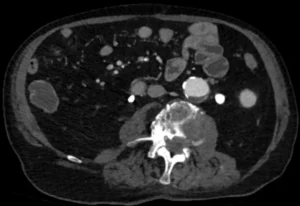

In the past, the only options for abdominal aortic aneurysm treatment were surveillance or surgery. Today endovascular repair of aortic aneurysms is usually the treatment of choice. Of course, choosing between surveillance, endovascular and surgical repair can be hard. It requires an understanding of the natural history of AAA as well as the short and…